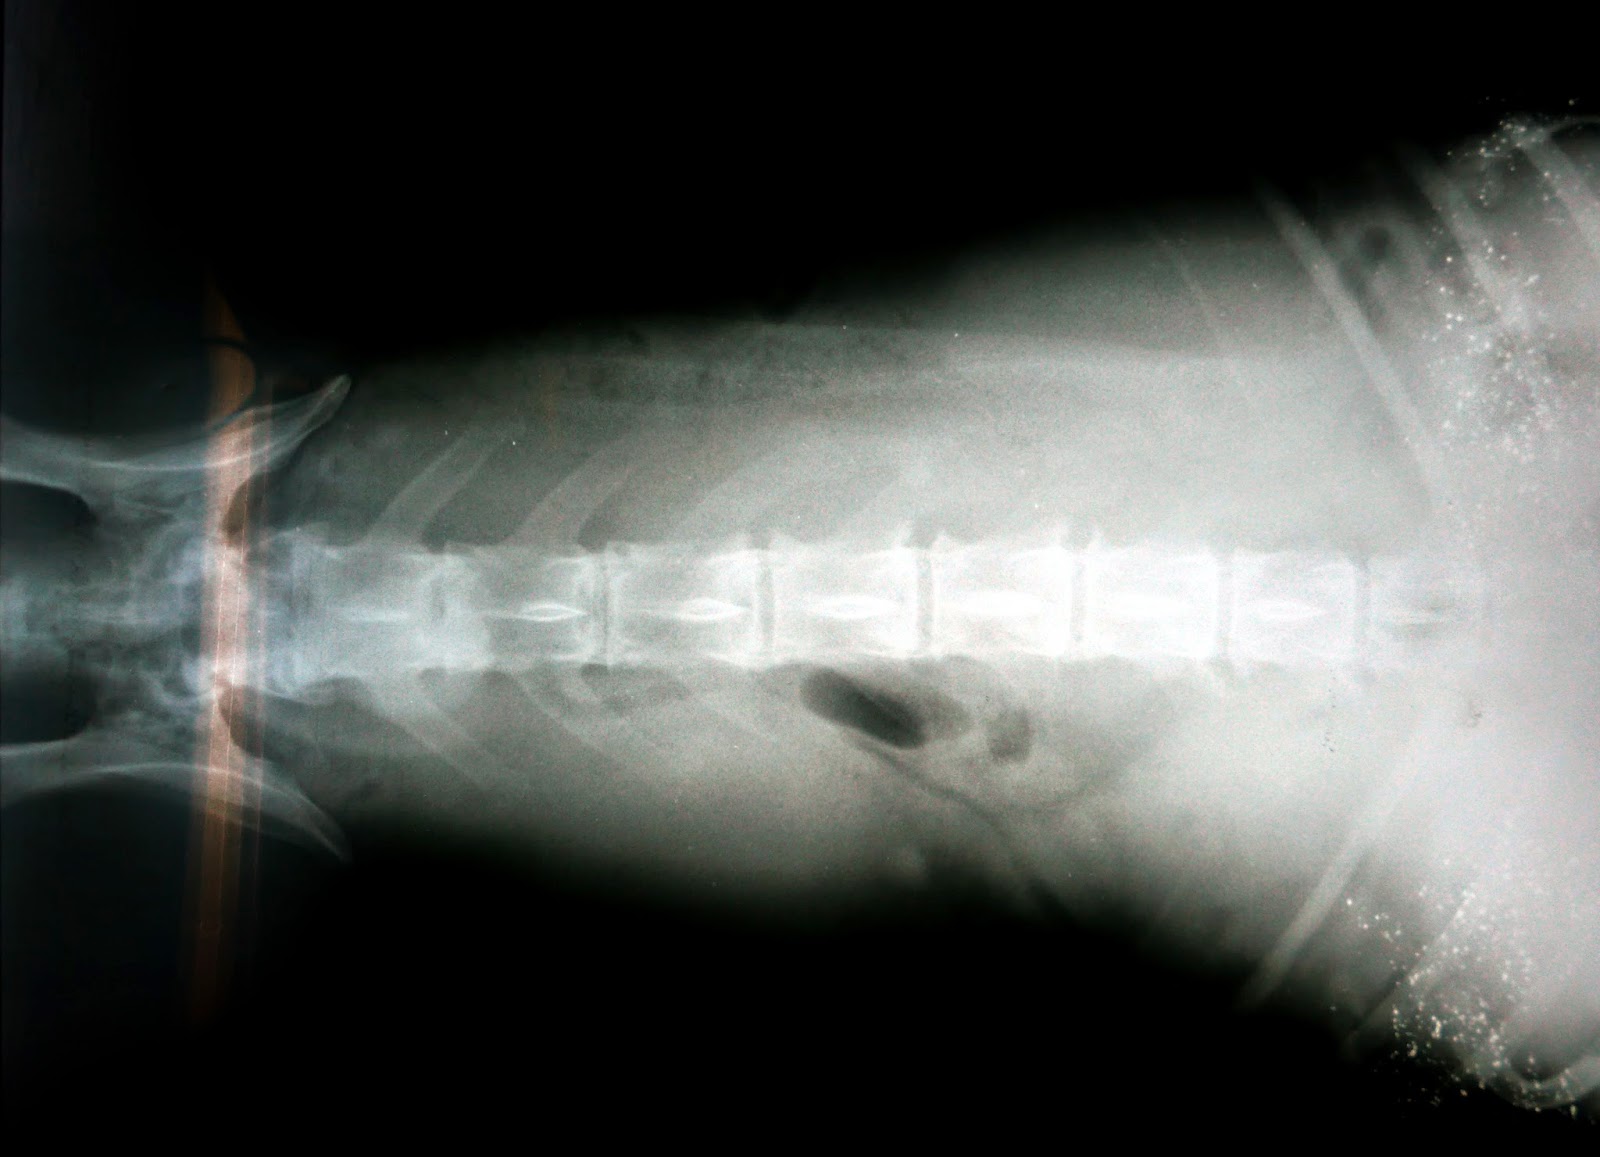

Tumor de bazo en perros

WebEl tumor de bazo es un tipo de cáncer que es común en perros y relativamente raro en los gatos y sus signos a menudo dependen de la localización del tumor, que van desde la. WebEn perros, del 0,3 al 2 por ciento de los tumores registrados se encuentran en las necropsias; el siete por ciento de todos los tumores son malignos; y alrededor del 50 por. WebCáncer de Bazo en perros. Al igual que los seres humanos, los perros y en general los animales domésticos pueden sufrir un sin número de enfermedades, entre. WebLos quistes sebáceos son un tipo de tumor benigno muy común en los perros. En pocas palabras, se producen por la acumulación de sebo, sustancia lipídica cuya función es. WebLas enfermedades más típicas que sufre el bazo son los tumores linfoma y hemangiosarcoma. El hemangiosarcoma es el tumor más frecuente en perros. Los. WebEl tumor de bazo es un tipo de cáncer que es común en perros y relativamente raro y sus signos a menudo dependen de la localización del tumor, que. WebSi es maligno ni que no reventar a terminará en metástasis y también, adiós perro. Si se opera hay mucho riesgo a que muera por su problema cardíaco, pero si sale bien y el.